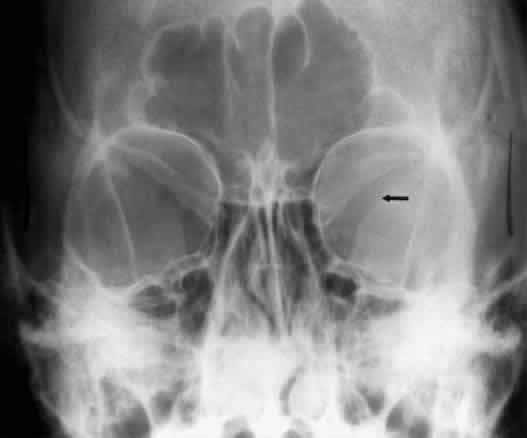

Hyperostosis of the orbital bones may be associated with a variety of disorders. The most common cause is a meningioma of the sphenoid bone (Fig. 14). Fibrous dysplasia, osteoblastic metastatic disease, or Paget's disease can also cause these bony changes. The orbital dimensions—orbital margin, superior orbital fissure, optic foramen—should be symmetric in size and shape. Mild asymmetry may be normal, but marked asymmetry should alert the clinician to search for pathologic causes. The vertical dimension of the orbit is best measured in the frontal plane with a nose-chin view as described by Lloyd.25 A difference of 2 mm or more is considered abnormal. The orbital dimensions can increase with any long-standing mass lesion that raises the intraorbital pressure. Lesions outside the muscle cone are more likely to cause localized enlargement, whereas intraconal lesions lead to a generalized orbital expansion. Such lesions include hemangiomas, optic nerve gliomas, meningiomas, and congenital glaucoma with buphthalmos or microphthalmos with cyst. Smaller orbits may be due to microphthalmos, enucleation in childhood, or congenital facial disorders. The superior orbital fissure has interpersonal and intrapersonal variations. The fissure should be symmetric, but there is no good measurement that identifies pathology, other than marked asymmetry. The fissure can be enlarged by infraclinoid aneurysm, carotid-cavernous fistulas, pituitary tumors, and meningiomas.26 Less common causes for enlargement include hemangiomas, lymphoma, mucocele of the sphenoid sinus, and neurofibromatosis (Fig. 15).